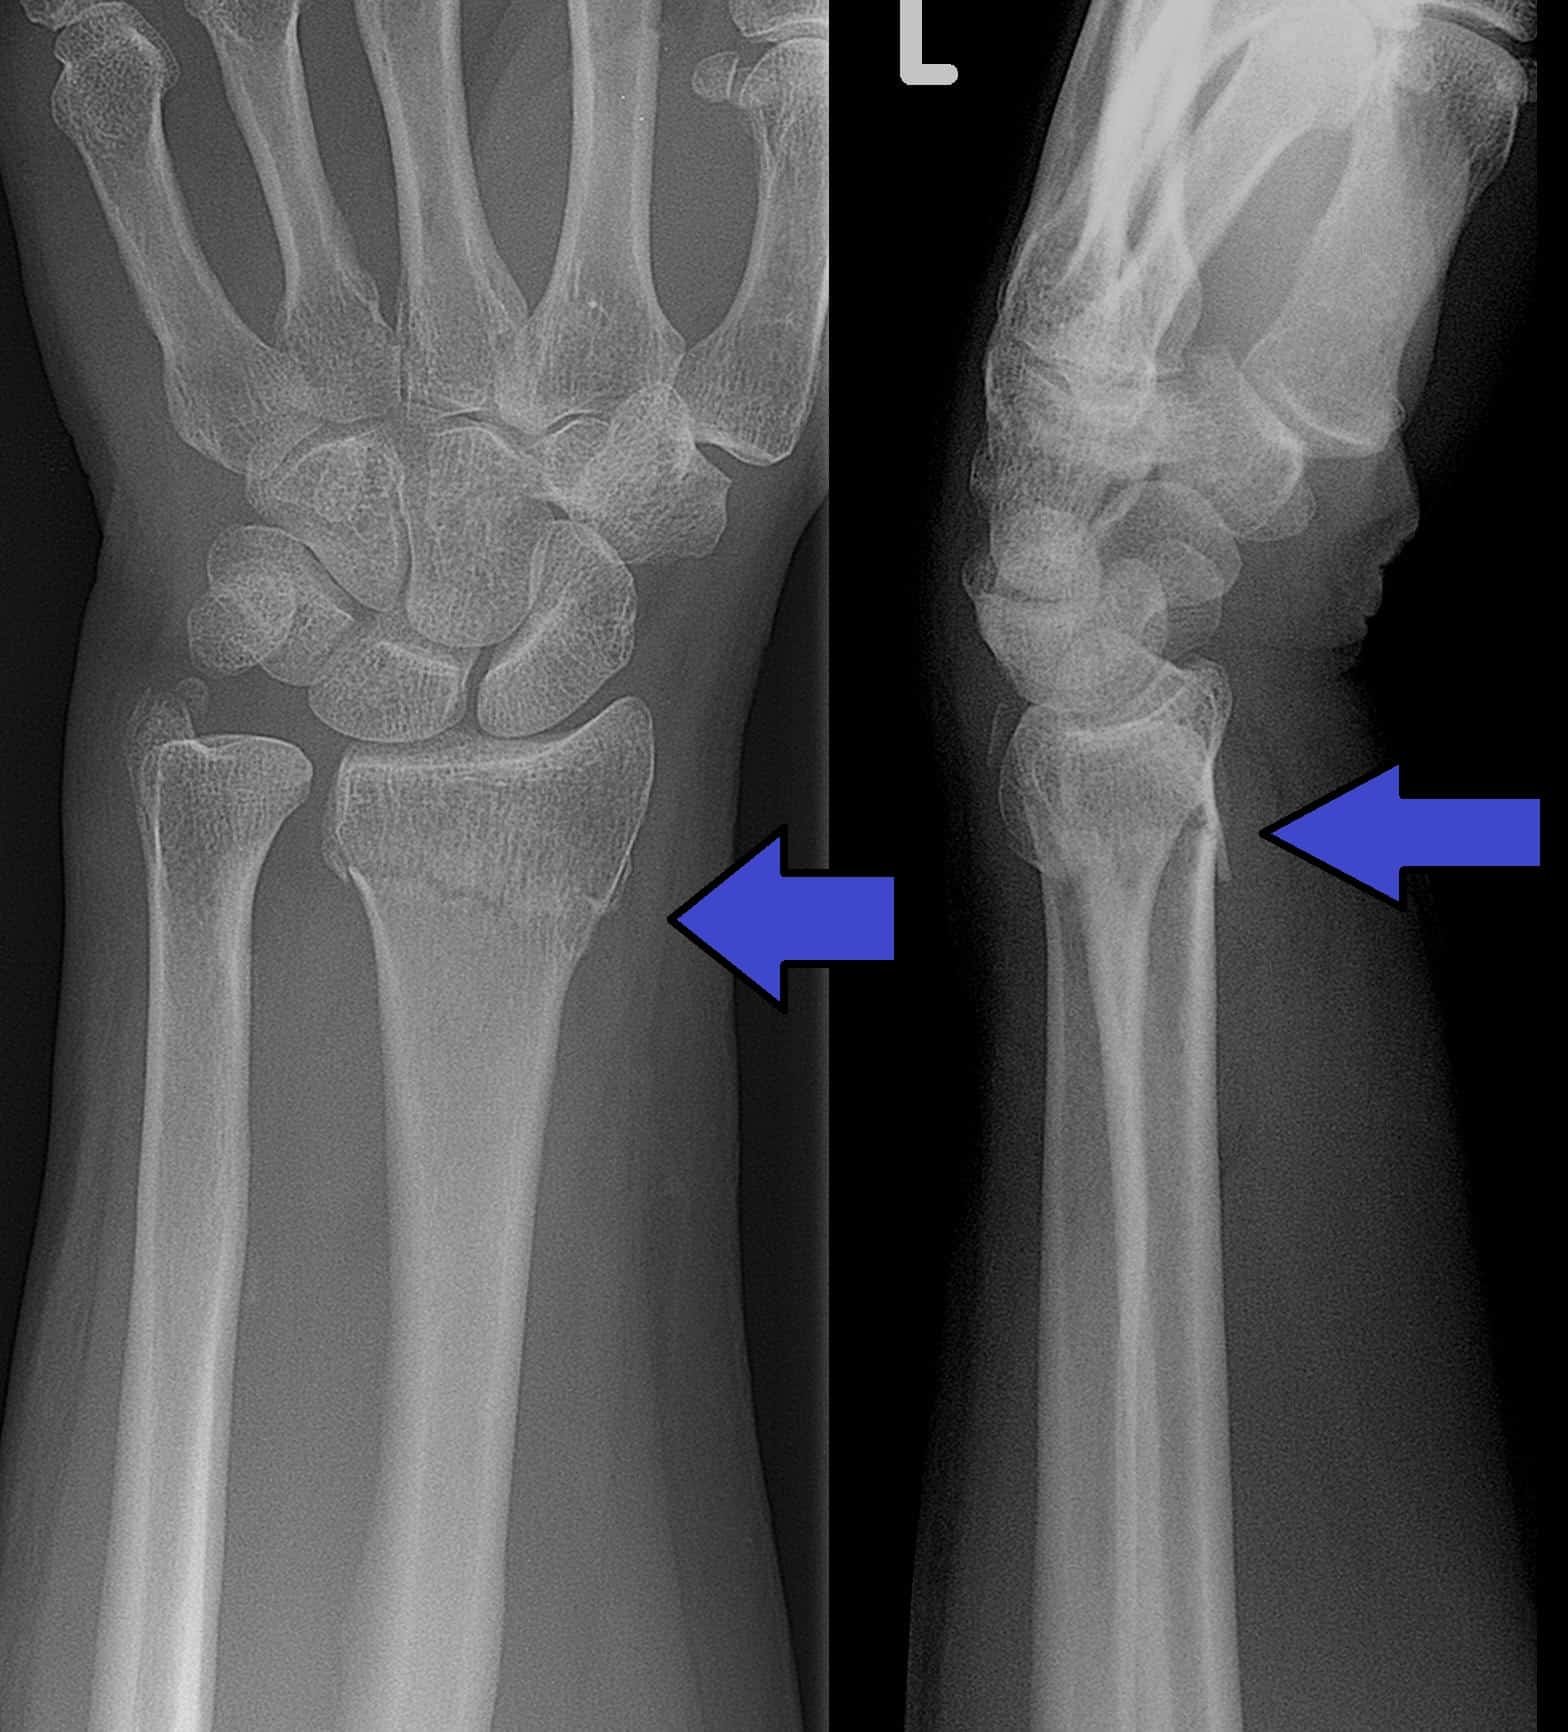

a) Colles fracture.

b) Fracture on fall in an outstretched hand:

- Colles fracture.

- Scaphoid fracture.